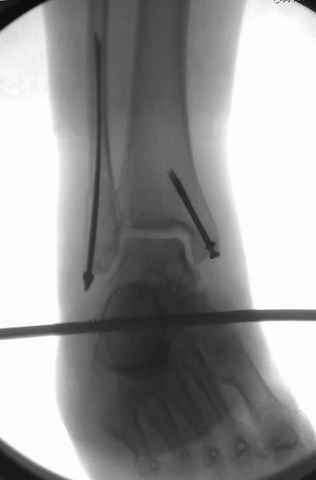

I would suggest to fix the fibular fracture at the very beginning and under fluoroscopical control and axial traction try to restore articular surface stabilizing percutanously by K wires and cannulated screws, type of external fixation to be used is up to your preference.

This is a pilon fracture. I suggest fixation of the fibula with a one-third tubular plate and a joint spanning external fixator on the medial side as initial treatment. If the tibial articular surface cannot be reconstituted, the patient will require an arthrodesis.

A propos fibular fixation if one is eager to stabilize it separately. In the fracture pattern a way of closed fixation by V-shaped stressed wire (advanced by colleagues from Moscow, prof. Lazarev A.F. et al.) must be excellent. We use indirect closed reduction by the external fixator. Example attached, that fibular fracture is even more suitable for plating but the wire did the job.